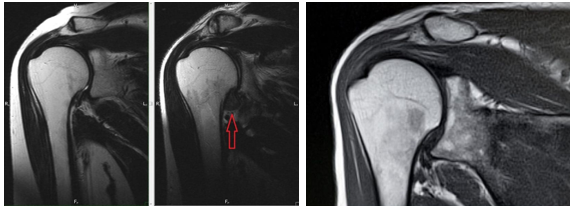

Высокую эффективность терапии препаратами коллагена для внутрисуставного и периартикулярного введения и геля на основе полинуклеотидов подтверждено результатом УЗИ исследованием и МРТ (рис.3, 4,5).

/Scherbakov.files/2.png)

А ˗ до лечения В – после лечения

А – до лечения: у пациента с адгезивным капсулитом определяется утолщение капсулы и уменьшение объема подмышечного заворота.

Основные проявления: боль и прогрессирующее снижение объема движений в плечевом суставе. В ˗ после лечения: у пациента восстановление капсулы и увеличение объема подмышечного заворота.

Отсутствие болевого синдрома и увеличение объема движений в плечевом суставе.

Рисунок 5. МРТ картина адгезивного капсулита до и после лечения